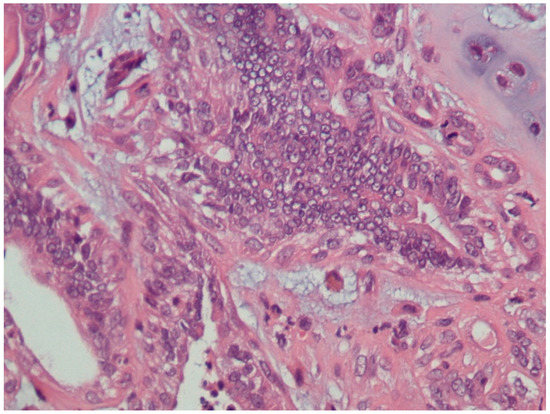

3.1. Histopathological Assessment